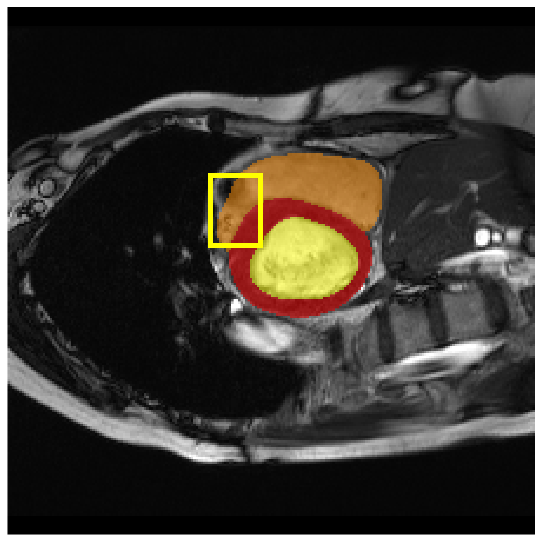

Our model is evaluated on the Synapse [25] and ACDC [24] datasets. Synapse is an abdominal CT image dataset with 30 images containing eight organs: the aorta, gallbladder (GB), left kidney (KL), right kidney (KR), liver, pancreas (PC), spleen (SP), and stomach (SM). 18 and 12 scans are used for training and evaluation, respectively. ACDC provides MRI data containing three organs of 100 patients: the right ventricle (RV), left ventricle (LV), and myocardium (Myo). 70 images for training, 10 for validation, and 20 images for evaluation are used.

4.3.2 Visual Comparisons

Visualization of our method on the Synapse and ACDC datasets is shown in Fig. 3(a) and Fig. 3(b). For the Synapse dataset illustrated in Fig. 3(a), FCT failed to accurately segment SM and GB, while MERIT achieved precise segmentation of SM but struggled with GB. In contrast, our method achieved accurate segmentation of both SM and GB. Regarding the ACDC dataset shown in Fig. 3(b), while previous methods achieve comparable segmentation of the Myo and LV to the GT, they exhibit noticeable errors on the RV, including invasion into adjacent organs and misrecognition. On the other hand, our method accurately segments across all three structures Myo, LV, and RV, performing as precisely as the GT. We demonstrate the superiority of our method quantitatively and qualitatively.